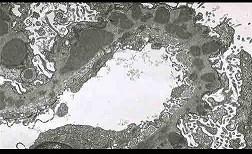

问题 光镜和电镜肾脏病理表现如下(图-1PAS基底膜增厚,中度系膜增生,图-2上皮下电子致密物沉积),其符合下面哪种病理类型 ( )

选项 A.膜性肾小球肾炎 B.局灶节段性肾小球硬化 C.膜增生性肾小球肾炎 D.肾小球轻微病变 E.局灶性肾炎

答案 A